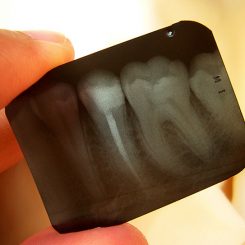

X-rays have become an incredibly valuable tool in modern medicine—especially for dentistry! We learn a lot from visually examining your child’s teeth, but not everything is visible to the naked eye during a routine dental exam.

Dental X-rays allow us to detect and diagnose tooth decay between teeth, on hard-to-reach surfaces, and under existing dental work. X-rays can even be helpful in identifying dental and orthodontic issues that exist beneath the gum line—something that was impossible without invasive procedures before X-rays became widely available.